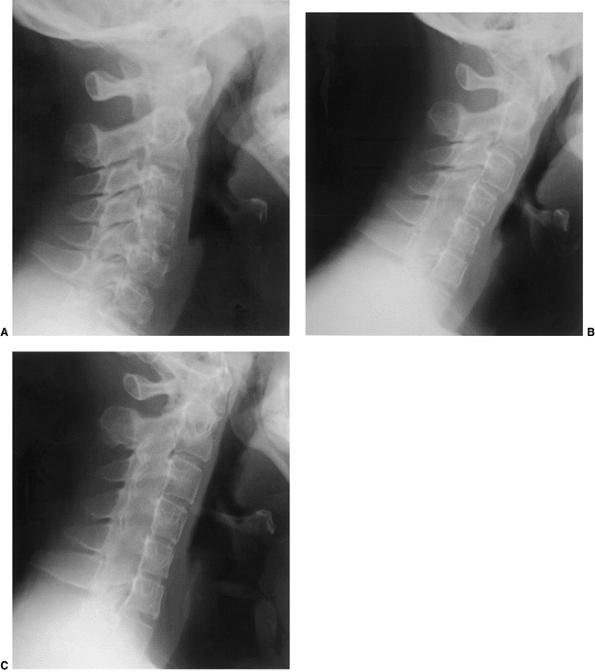

Figure 22.6 A: The posterior cervical line referred to by Swischuk. In C2-C3 pseudosubluxation, the posterior cervical line may pass through (a), touch (b), or lie 1 mm in front of (c) the cortex of the posterior arch of C2. B and C:

Lateral cervical radiographs of a child 2 years and 6 months of age with pseudosubluxation at C2-C3. The radiograph in extension (B) demonstrates no step-off at C2-C3, whereas the radiograph in flexion (C) demonstrates a step-off at C2-C3 (arrow), but with a normal posterior cervical line (solid line). Also note the anterior wedging of the C3 vertebral body, and the overriding of the anterior arch of the atlas on the tip of the odontoid in extension. (A from Shaw M, Burnett H, Wilson A, et al. Pseudosubluxation of C2 on C3 in polytraumatized children—prevalence and significance. Clin Radiol 1999;54:377–380, with permision.) |